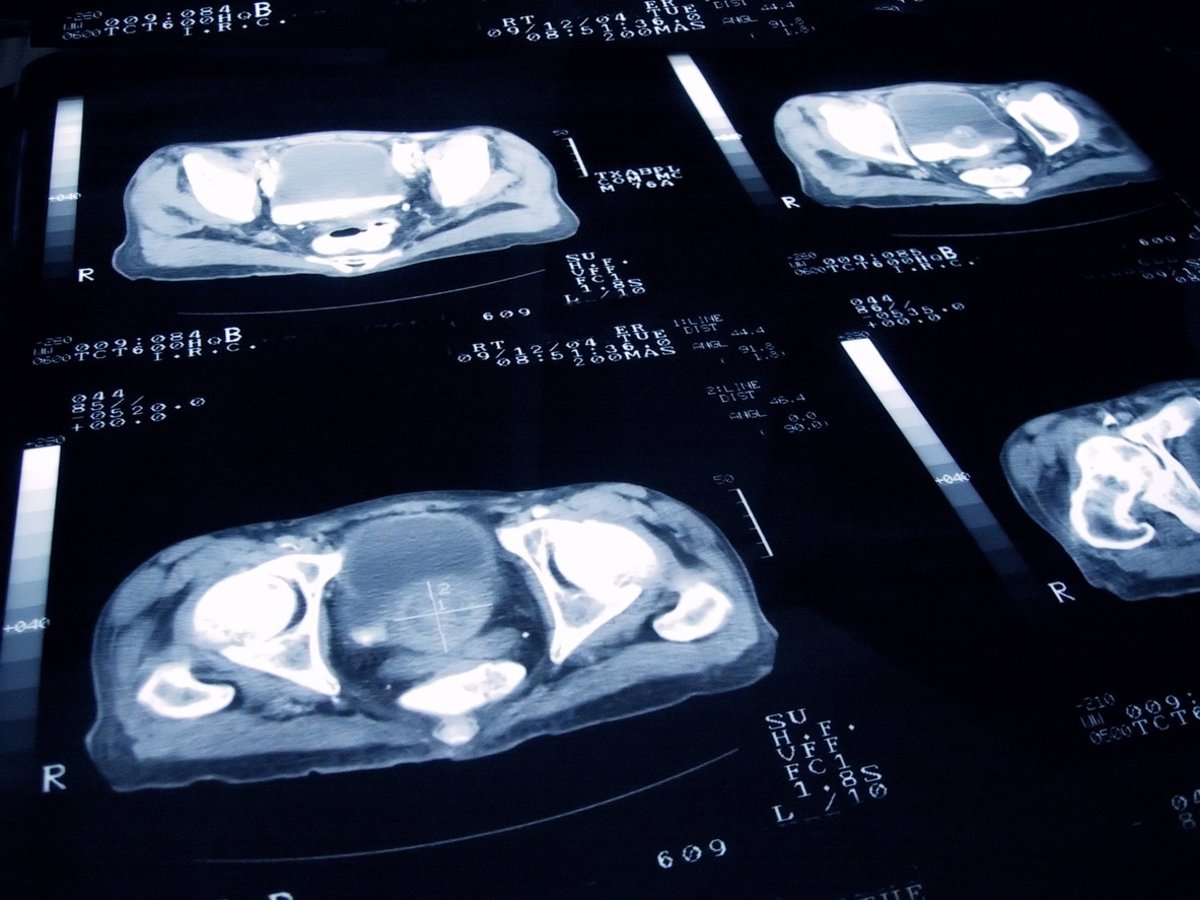

Archivo - Arquivo - Câncer de próstata

JAMESBENET/ ISTOCK - Arquivo